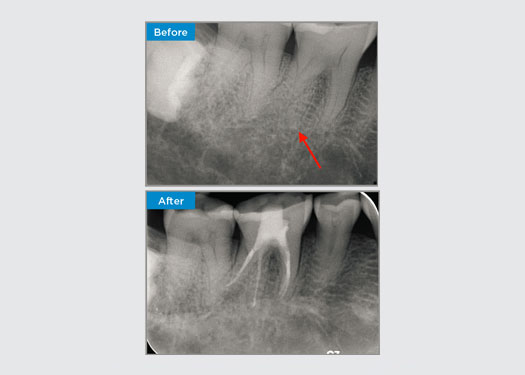

Patiënt presenteerde zich met asymptomatische apicale parodontitis op tand 34. Op basis van de preoperatieve röntgenfoto werd tand 34 opgemerkt met twee zichtbare wortels. Een CBCT-scan bevestigde echter een driewortelige premolaar en de kanalen waren in drieën verdeeld bij de middenwortel. Een zorgvuldige selectie van bestanden is cruciaal voor deze delicate tand.

Dr. Jack Lin, endodontist, Sydney, NSW Australië

In deze situatie is het behoud van de tand-/wortelstructuur essentieel om het risico op richels, transport, ritsen, perforatie en wortelbreuk te verminderen. Casusselectie, diagnose en planning vóór de behandeling zijn belangrijk. Endodontische vijlselectie met flexibiliteit, efficiëntie en respect voor de natuurlijke wortelanatomie is van cruciaal belang.